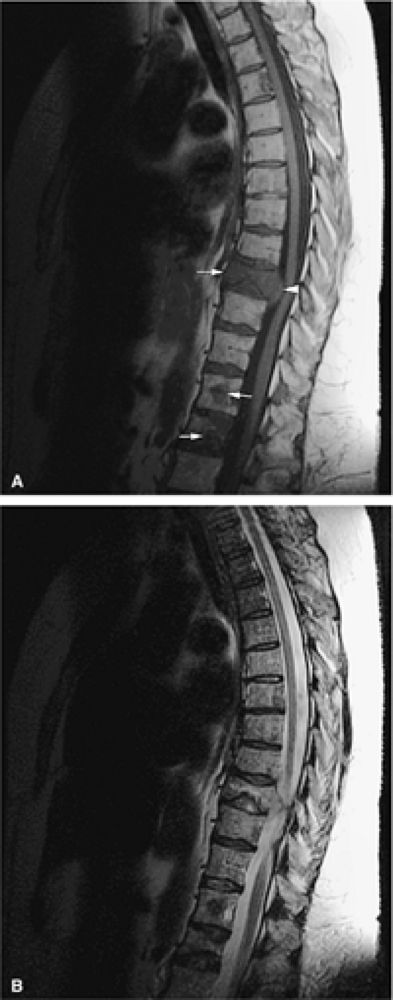

![]() |

FIGURE 13.16 ● Marrow response to chemotherapy. T1-weighted images of the lumbar spine before chemotherapy (A) and after chemotherapy (B) for metastatic colon carcinoma. Metastatic disease demonstrates low signal intensity at L2 and L4 prior to chemotherapy. High-signal-intensity fatty replacement can be seen after chemotherapy. Adjacent uninvolved vertebral bodies also show a flip-flop in signal intensity as the red marrow is activated.